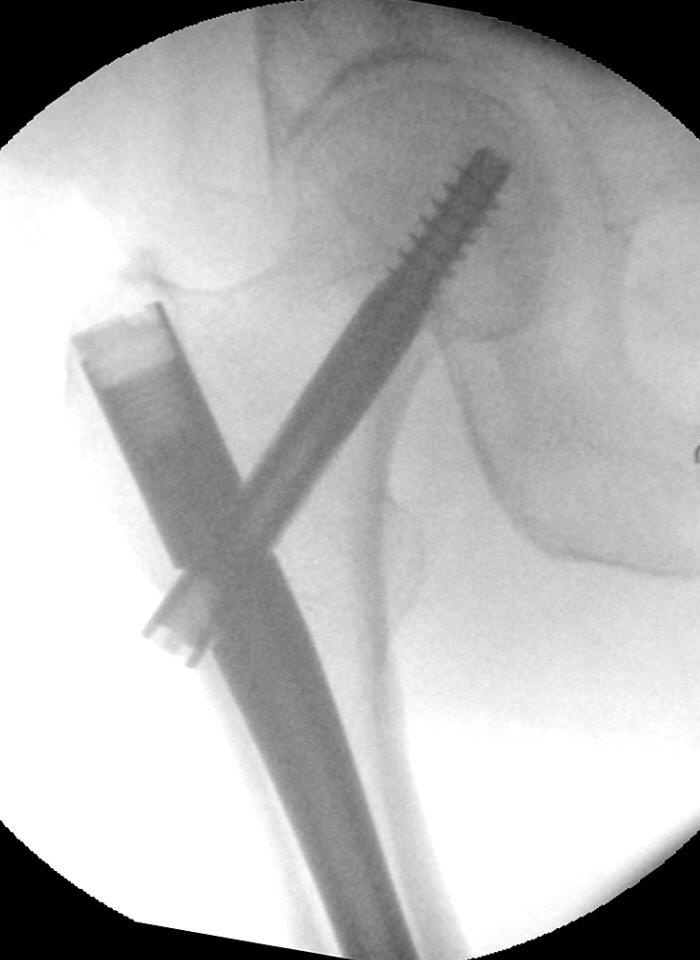

- Se till att sidobilden är exakt rak, man kan behöva rotera röntgenapparaten. Det runda hålet i spiken ska vara runt, och det avlånga hålet ska vara avlångt, utan några dubbelkonturer.

- Markera i frontalvy exakt var mitten av hålet är

- Markera i sidobild exakt mitten av hålet, använd gärna kniv

Knivspets markerar placering av statisk distal låsskruv. Notera att bilden är tagen exakt rakt från sidan.

- Gör hudsnitt

- För in pryl och kontrollera i både frontalvy och sidovy att spetsen är exakt mitt i hålet. Gör ordentligt märke.

- Borra i prylens hål, kontrollera i både frontal- och sidovy att du är mitt i hålet och med rätt vinkel.